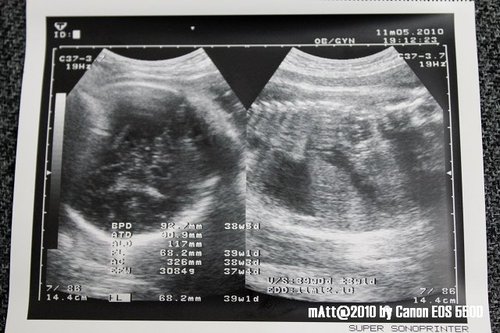

2010/11/05

第12次產檢 38W4D

上回醫生驚呼玩子的體重成長速度很快

導致EP擔心玩子長太大會不好生...

所以今天再請醫生好好的量一下玩子的體重

結果是3084g !!

呼這樣還差不多